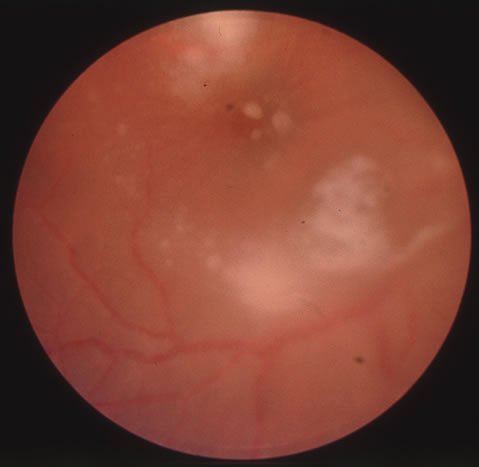

In primary ocular HSV infections, a severe follicular conjunctivitis with regional adenopathy is present. Vesicles may appear on the eyelid skin or lid margin, producing blepharitis (Fig. 3). Corneal involvement initially takes the form of a superficial punctate keratitis, which may progress to dendritic or geographic ulceration. Stromal infiltrates and uveitis are less common and relatively mild in primary disease. In uncomplicated cases, lesions usually heal completely in 2 to 3 weeks without scarring. Most cases of ocular HSV are recurrences. Recrudescent ocular herpes may take the form of dendritic or geographic ulcers, recurrent erosions, interstitial or disciform stromal keratitis, and anterior uveitis.3 HSV may also be an agent of retinitis and acute retinal necrosis (Fig. 4).

Corneal complications occur in the majority of patients with herpes zoster ophthalmicus. A punctate epithelial keratopathy with pseudodendrite formation is the earliest and most common lesion that occurs. Stromal infiltrates, disciform reactions, and rarely interstitial keratitis are also observed. Scarring and contracture of the lid margin often results in trichiasis, distichiasis, entropion, or ectropion. Corneal sensation is reduced, and neurotrophic ulceration, corneal melting, or perforation may ensue. Extraocular muscle involvement with facial paresis has been observed.11 The acute retinal necrosis (ARN) syndrome is most often caused by the herpes zoster virus, although occasionally it may be a result of herpes simplex infection.12 It is typically described in healthy patients although association with immunosuppressed patients has also been described. Granular, nonhemorrhagic areas of retinal necrosis may be observed in the fundus, often rapidly coalescing with resulting blindness often caused by retinal detachment. There is often an associated vasculitis and vitritis. In immunocompromised patients VZV or HSV retinitis may also take the pattern of progressive outer retinal necrosis (PORN) (Fig. 6). PORN differs from ARN in that the former is multifocal, localized to the outer retina, and is less often associated with vasculitis and vitritis.